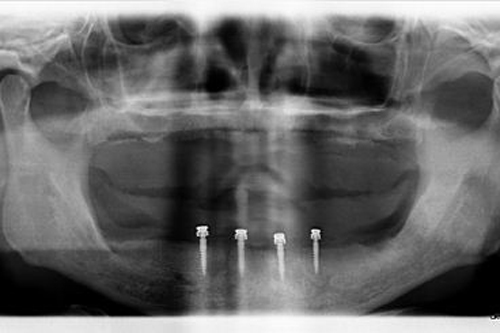

1. Initial Consultation

The first step is to have a consultation with one of our experienced dental surgeons. They will conduct a thorough examination of your mouth, including taking x-rays. X-rays help the dentist determine your eligibility for dental implants, as it lets them see the condition of the bone that will support your new teeth.

The dentist will also talk about your expectations for the treatment, and answer any questions that you have.

3. Implant Placement

Before beginning implant placement, the dental surgeon administers anesthetic. Then, they drill a hole into the jawbone. The position and angle of this hole are carefully planned to ensure maximum stability and longevity.

The implant itself is then screwed into the hole and tightened.

Sometimes the gum is stitched over the implant while it heals. Other times, a healing cap is applied. This looks like a small metal disc that sits above the gumline.